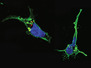

Like a fast-flowing river, the bloodstream carries white blood cells – the first responders of our immune system, also called leucocytes – to areas of infection in the body. This high-speed journey is fraught with danger. To prevent the currents from washing the leucocytes away once they arrive, they do what any salty sea dog would – drop their anchors. The leucocytes pictured here (the largest of which is 2,000 times smaller than a Fisherman’s Friend) were scattered over a man-made surface similar to the lining of a blood vessel and then blasted with fast-flowing liquid to simulate the bloodstream. Prickly anchors developed immediately to tether the base of the cell to the vessel-like floor. Only after a dramatic voyage inside our blood vessels can the job of the leucocytes really begin, penetrating through the vessel lining on a mission to tackle a nearby infection.